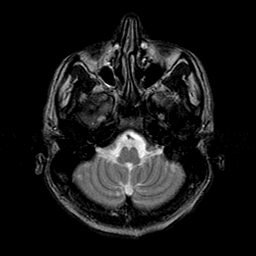

Sarcoma, MR Study #1 mr-t2 -- Slice #3

[Home][Help][Clinical] Slice 3